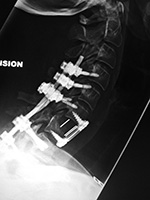

Cervical spine anterior and posterior fusion Cervical spine anterior and posterior fusion with intervertebral bone struts (plugs)

Anterior and posterior cervical spine fusion AP view Anterior and posterior cervical spine fusion lateral view Anterior and cervical spine fusion with intervertebral bone struts Anterior and cervical spine fusion with intervertebral bone struts

Young woman with traumatic locked facets at C6-7 and C7 body fracture. A posterior cervical fusion with lateral mass screws (cervical spine) and pedicle screws (thoracic spine) and rods extends from C4 to T2. There is an anterior cervical fusion plate and screws at C6-7 with a intervertebral disk cage at C6-7 and a crosslink at C6. There is an anterior cervical fusion plate that extends from C3 to C7 and posterior lateral mass screws and rods on each side from C3 to C7. Intervertebral bone struts (plugs) are present at the disk spaces from C3 to C6.